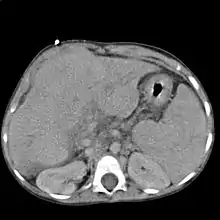

Le scanner et l'IRM sont meilleurs que l'échographie pour détecter un cancer du foie[2]. L'IRM est également fiable pour détecter certaines causes, notamment l'hémochromatose, par la mesure de la concentration en fer des tissus[15]. La fibroscopie œsogastrique peut retrouver des varices œsophagiennes, signe d'hypertension portale.